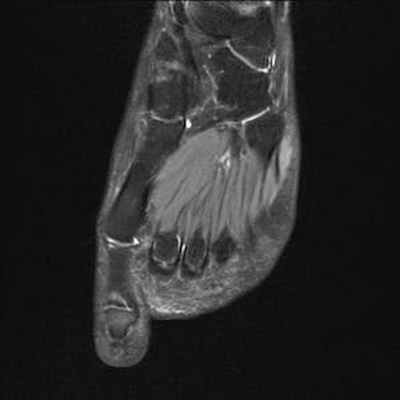

Головка 2-ой плюсневой кости выглядит сплюснутой и расширенной с правой стороны в связи с болезнью Фрейберга.

Отсутствие внутрикостной отёчной инфильтрации по краям суставной щели плюснефалангового сустава. Напротив, следует отметить наличие внутрисуставного выпота.

Для диагностики заболевания обычно бывает достаточно обычной рентгенографии, но иногда доктор может назначить МРТ либо исследование радиоизотопным методом.

Сначала будет сделан рентгеновский снимок, но его недостаток в том, что он может не показать Фрейберга на ранней стадии. Один МРТ обследование - самый полезный инструмент для раннего обнаружения Фрайберга. Исследование 3D CT может дать хорошее представление о том, насколько обширны повреждения от некроза.

МРТ также может использоваться для оценки состояния, и помочь в раннем выявлении болезни Фрейберга, когда рентгенограммы не имеют изменений. Другие исследования, такие как лабораторные исследования, также могут быть рекомендованы для исключения других состояний, вызывающих подобные симптомы.